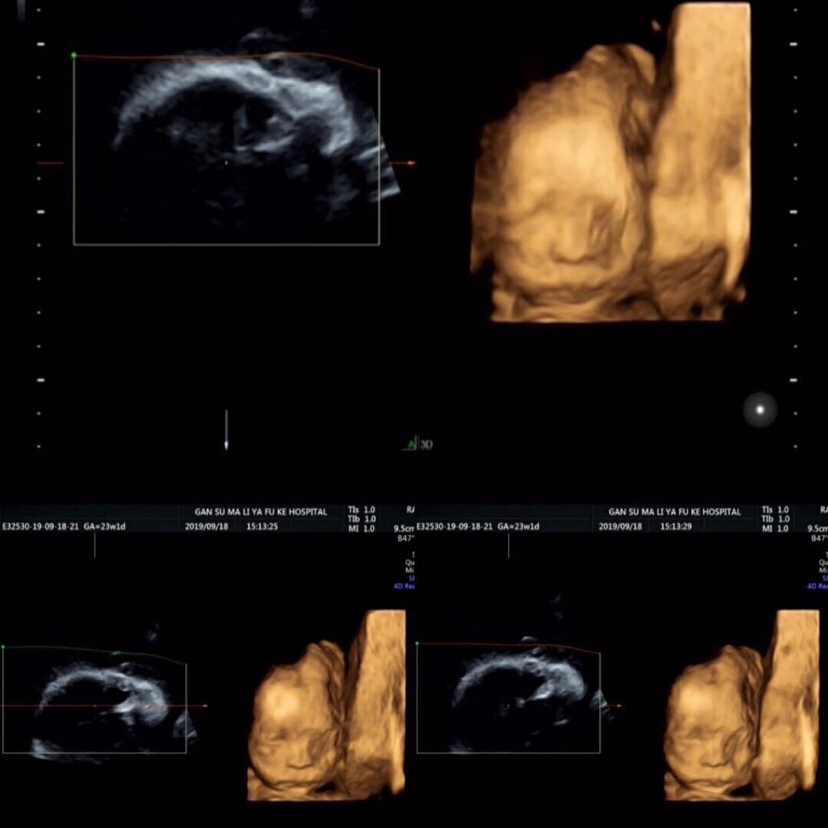

孕32周+4天